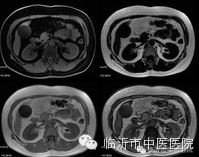

在腹部扫描中提高了病变组织的检出率,有效的消除运动、金属及磁敏感伪影,图像清晰,分辨率高。

MRCP具有无创性、无需插管、不需要注射造影剂、安全可靠和患者无痛苦等优点,易被患者所接受。